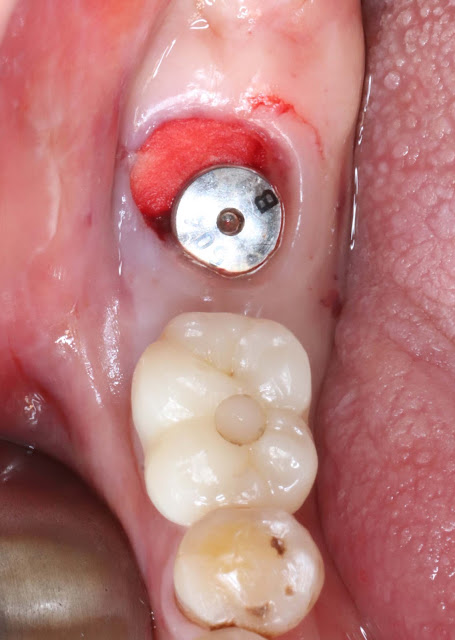

A 79-year-old male patient with chronic periodontitis in the #47 region, exhibiting significant mobility but not severe bone resorption, underwent extraction with immediate implant placement due to the mobility issue.

The implant is completely submerged within the bone, and it was placed with an approximate depth of around 4mm to achieve a proper gingival height.

Collagen plug was used to prevent the penetration of foreign substances without performing separate bone grafting.

Afterward, no sutures were applied, and Periopack was maintained. Bone healing abutment (size 604) was placed to avoid interference with adjacent bone.